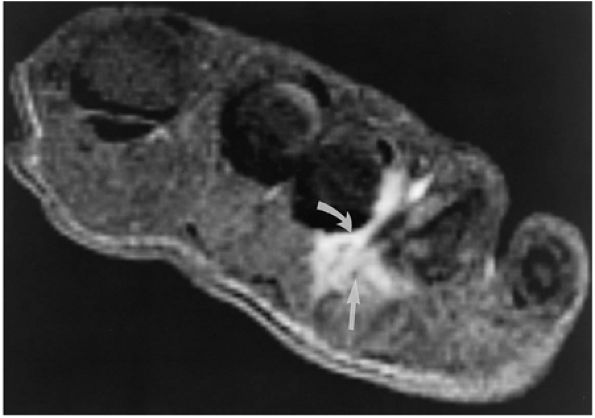

FIGURE 5.27 ● Axial anatomy of the ankle and foot. (A) The flexor digitorum longus, flexor hallucis longus, peroneus brevis, soleus, and extensor digitorum muscles are examined at this level for strain, tears, or fatty atrophy that may suggest denervation. (B) The tibialis anterior, extensor hallucis longus, and extensor digitorum longus tendons are examined on every ankle MR examination. Extensor tendon pathology is frequently overlooked if these tendons are not included as part of the ankle checklist. (C) Tears and sprains of the anterior syndesmotic ligament are a frequent cause of persistent ankle pain following ankle sprain. The syndesmotic ligaments are thick, tough ligaments that are important ankle stabilizers, and delayed diagnosis of syndesmotic tears may result in significant degenerative arthrosis at the tibiotalar joint due to the resulting ankle instability. The syndesmotic ligaments course obliquely inferiorly from the tibia to the fibula and are not usually visualized in their entirety on a single axial image; rather, their course is followed on at least two or three successive axial images. (D) The peripheral margin of the peroneal tendons and tibialis posterior tendon should normally never extend beyond the peripheral margins of the lateral and medial malleoli, respectively. Tendon subluxation around the posterior corner of either malleolus is indicative of a tear of the overlying flexor retinaculum (medially) or peroneal retinaculum (laterally). When the retinacula are torn, the tendon is free to intermittently sublux or dislocate, leading to tendon degeneration, pain, and tendon dysfunction. (E) Suspected osteochondral lesions of the talar dome are visualized and further characterized on axial images through the top of the talar dome. (F) The peroneus brevis tendon may normally appear somewhat flattened. However, as the tendon degenerates, it becomes U-shaped and drapes around the anterior aspect of the peroneus longus and becomes impinged between the peroneus longus tendon and the lateral malleolus. With further degeneration, the peroneus brevis may split or completely rupture. (G) Evidence of anterior talofibular ligament injury is visualized on the majority of MR ankle examinations and appears as thickening, intermediate signal with ill-defined fibers, or attenuation of the ligament. This is commonly asymptomatic. (H) Because the flexor hallucis longus tendon sheath communicates with the tibiotalar joint, fluid may normally be present within the tendon sheath in proportion to the amount of fluid in the tibiotalar joint. If there is fluid within the tendon sheath out of proportion to that seen in the tibiotalar joint, tenosynovitis is most likely present. The finding of flexor hallucis longus tenosynovitis should prompt a search for an os trigonum, as impingement of the flexor hallucis longus tendon between an os trigonum and the posterior tibial plafond is a common cause for FHL tenosynovitis. (I) The calcaneofibular ligament (CFL) passes anterior and medial to the peroneal tendons. On the image at which the CFL passes directly medial to the peroneus brevis tendon, the appearance of the peroneus brevis and the CFL side by side is occasionally mistaken for a split peroneus brevis tendon. (J) Dilated posterior tibial veins within the tarsal tunnel occasionally compresses the tibial nerve. In the setting of clinical suspicion for tarsal tunnel syndrome or if there is evidence of muscle denervation on MR images, the size of the posterior tibial veins should be described. (K) The spring ligament is identified at this axial image location, extending from the anteromedial calcaneus to the posteromedial navicular. Tears of the spring ligament may result in medial instability and hindfoot valgus. (L) The posterior tibialis tendon (PTT) may normally become thickened and fan-like as it passes posterior to its navicular insertion (prior to also inserting on the cuneiforms and the base of the second through fourth metatarsals). In the absence of other findings, the thickening of the PTT at this level should not be mistaken for focal tendinosis. (M) On inferior images through the ankle, Lisfranc's ligament is occasionally included in the FOV. Lisfranc's ligament extends from the medial cuneiform to the base of the second metatarsal. If Lisfranc's ligament is included in the FOV, the status of the ligament should be described, as undiagnosed Lisfranc ligament tears can lead to debilitating midfoot arthrosis. (N) As the medial and lateral tendons turn from their vertical course to a horizontal course along the plantar aspect of the foot, the tendons may demonstrate a magic-angle artifact, causing the tendons to appear gray on short-TE images, mimicking tendinosis. Correlation with images using longer TE values is advised in such situations.